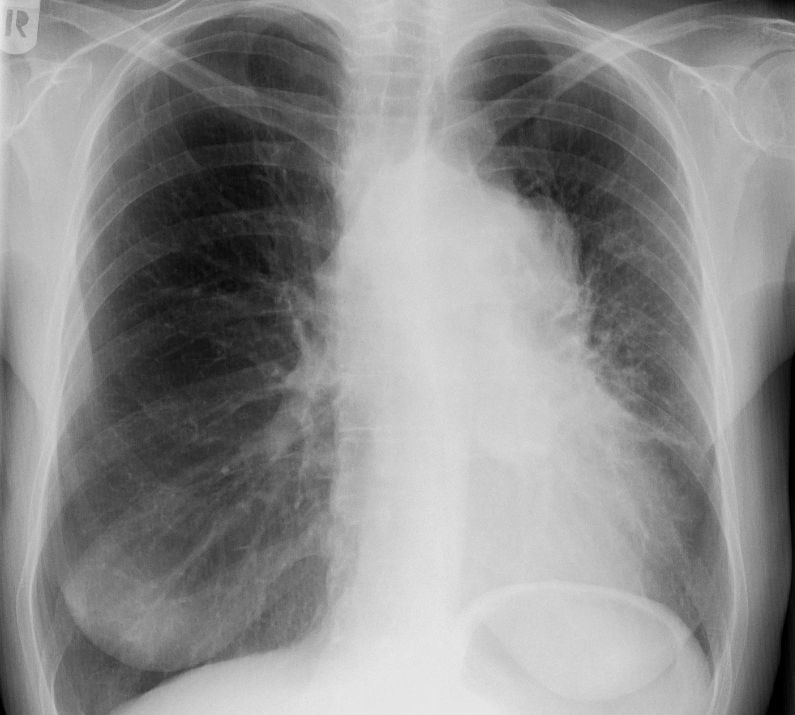

Röntgen Thorax

Kleinzelliges Bronchialkarzinom des rechten Hauptbronchus T4 N2 M1bra.

Kleinzelliges Bronchialkarzinom des rechten Unterlappen T2 N2 M0.

53-jährige Frau mit Dyspnoe und Zeichen der oberen Einflusstauung. Kleinzelliges Bronchialkarzinom rechts zentral.